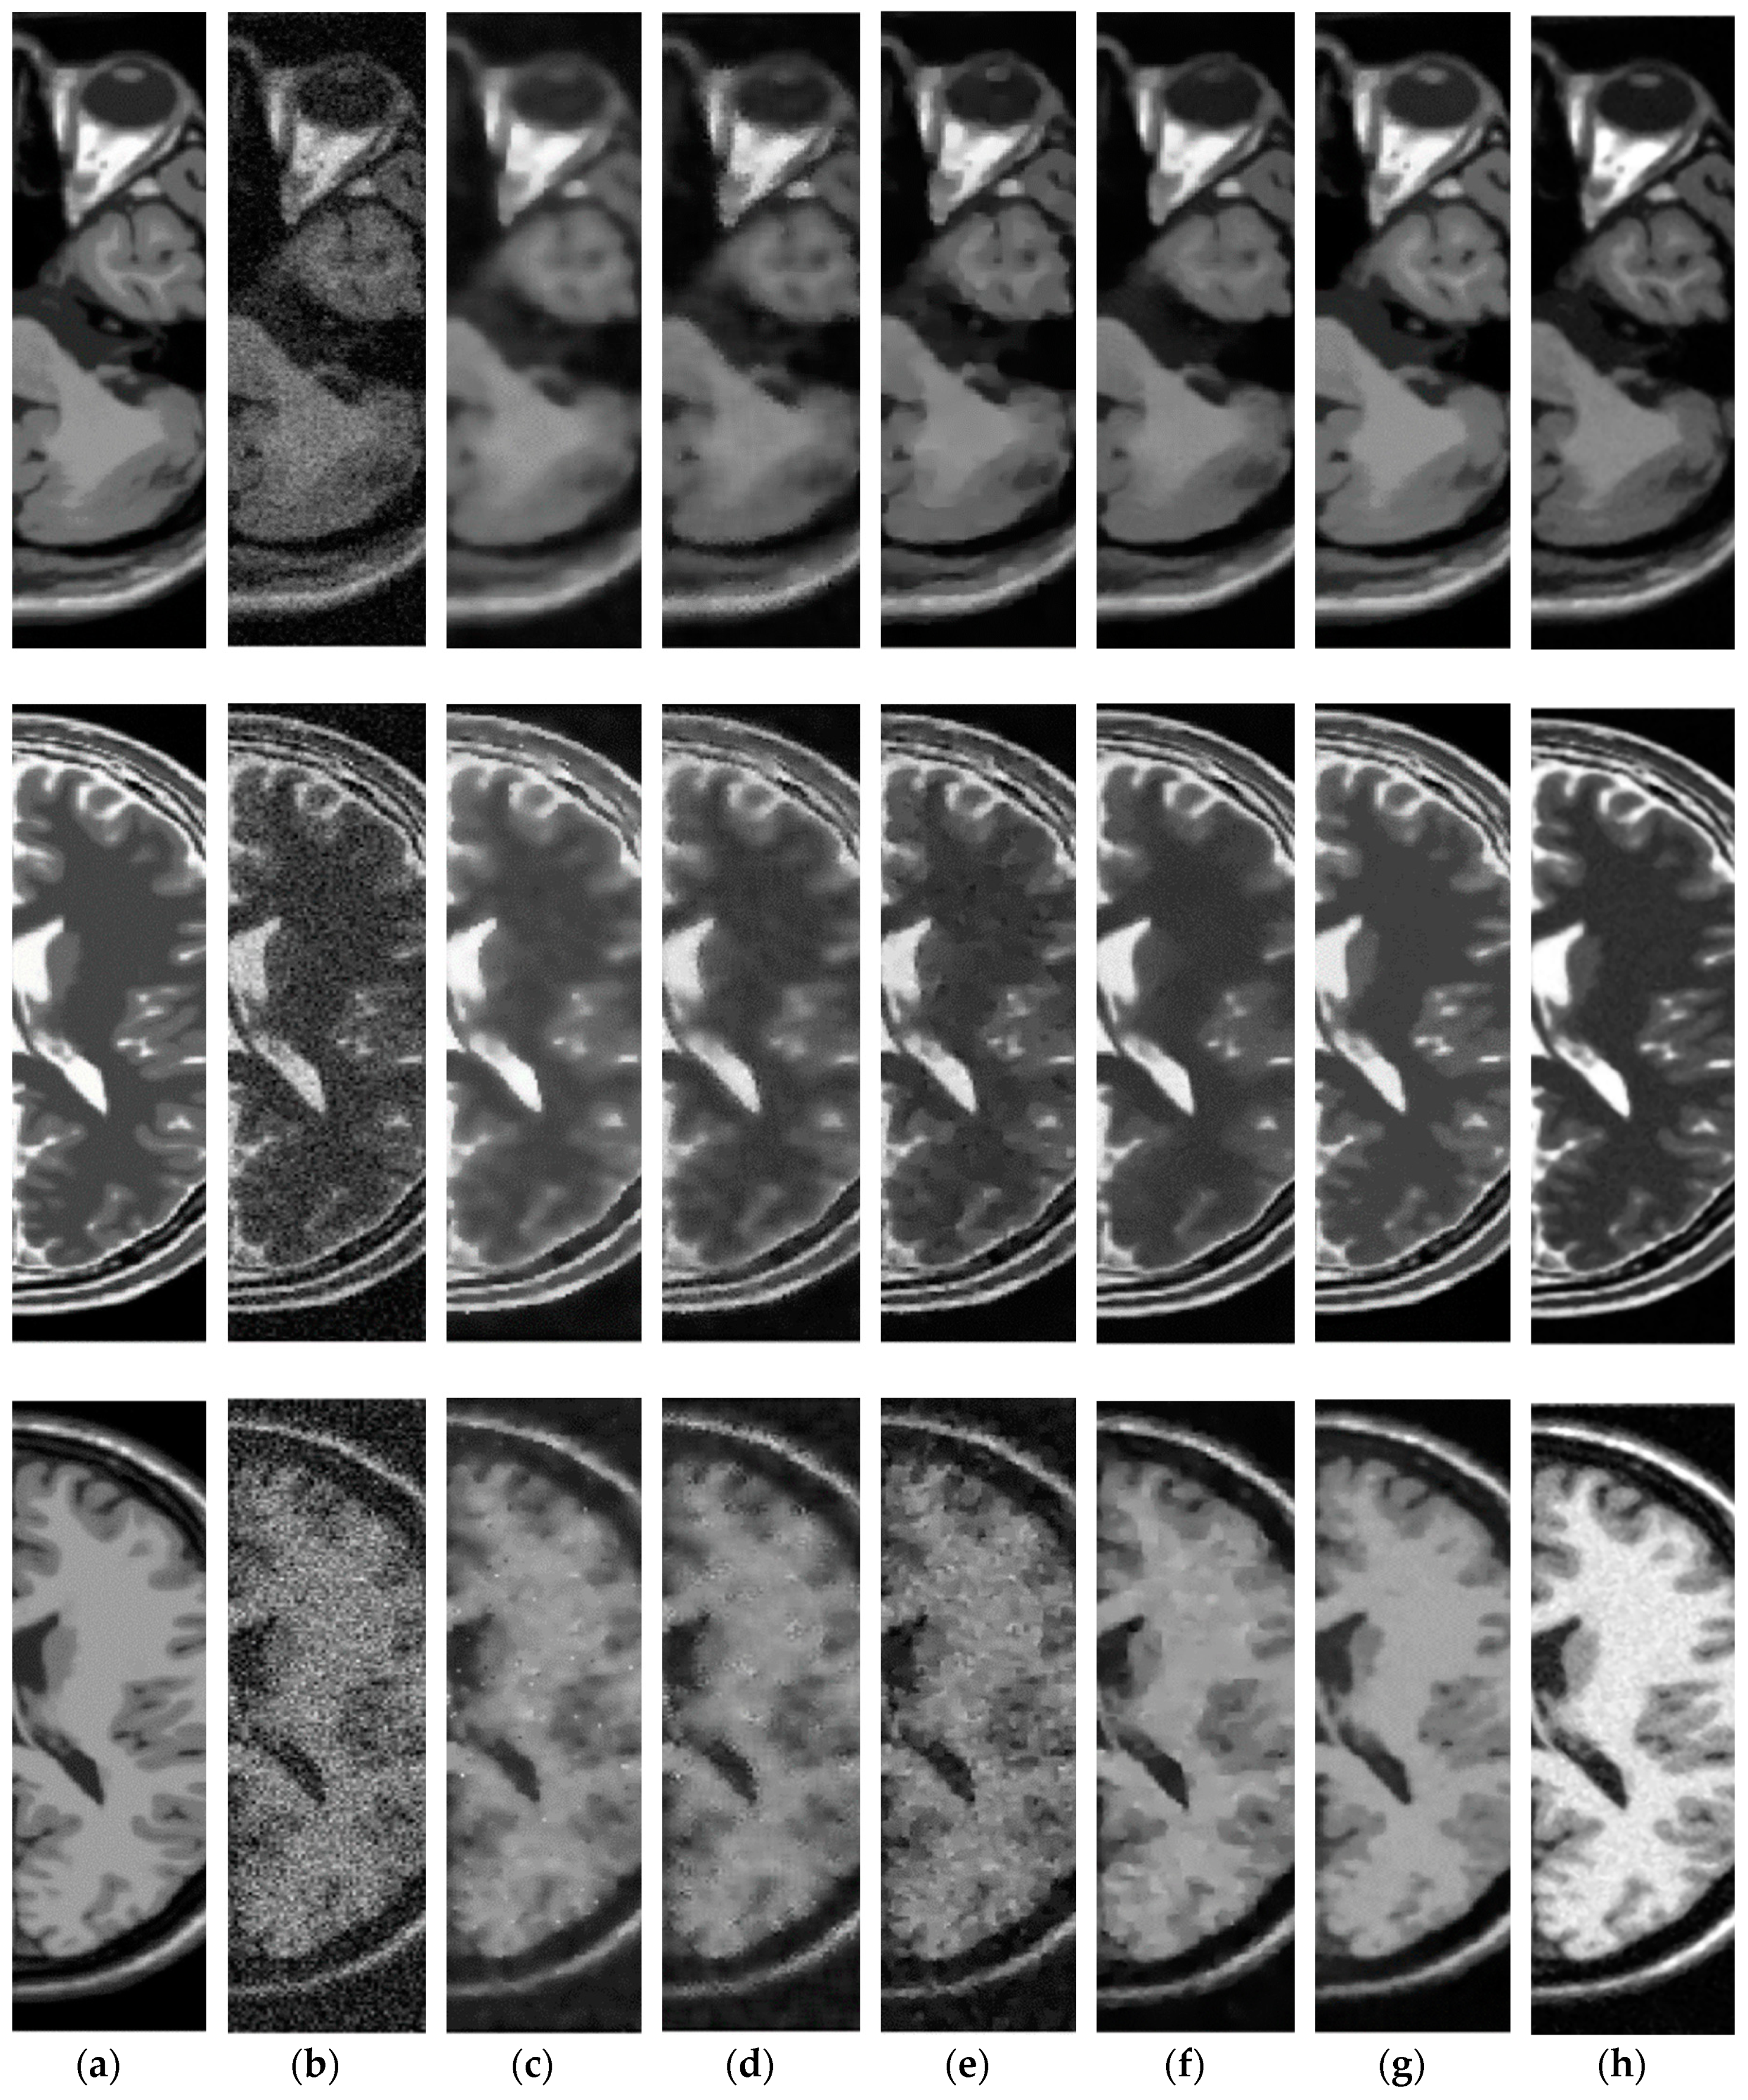

3.3. Comparative Performance in Simulated MRI

3.4. Comparative Performance in Real MRI